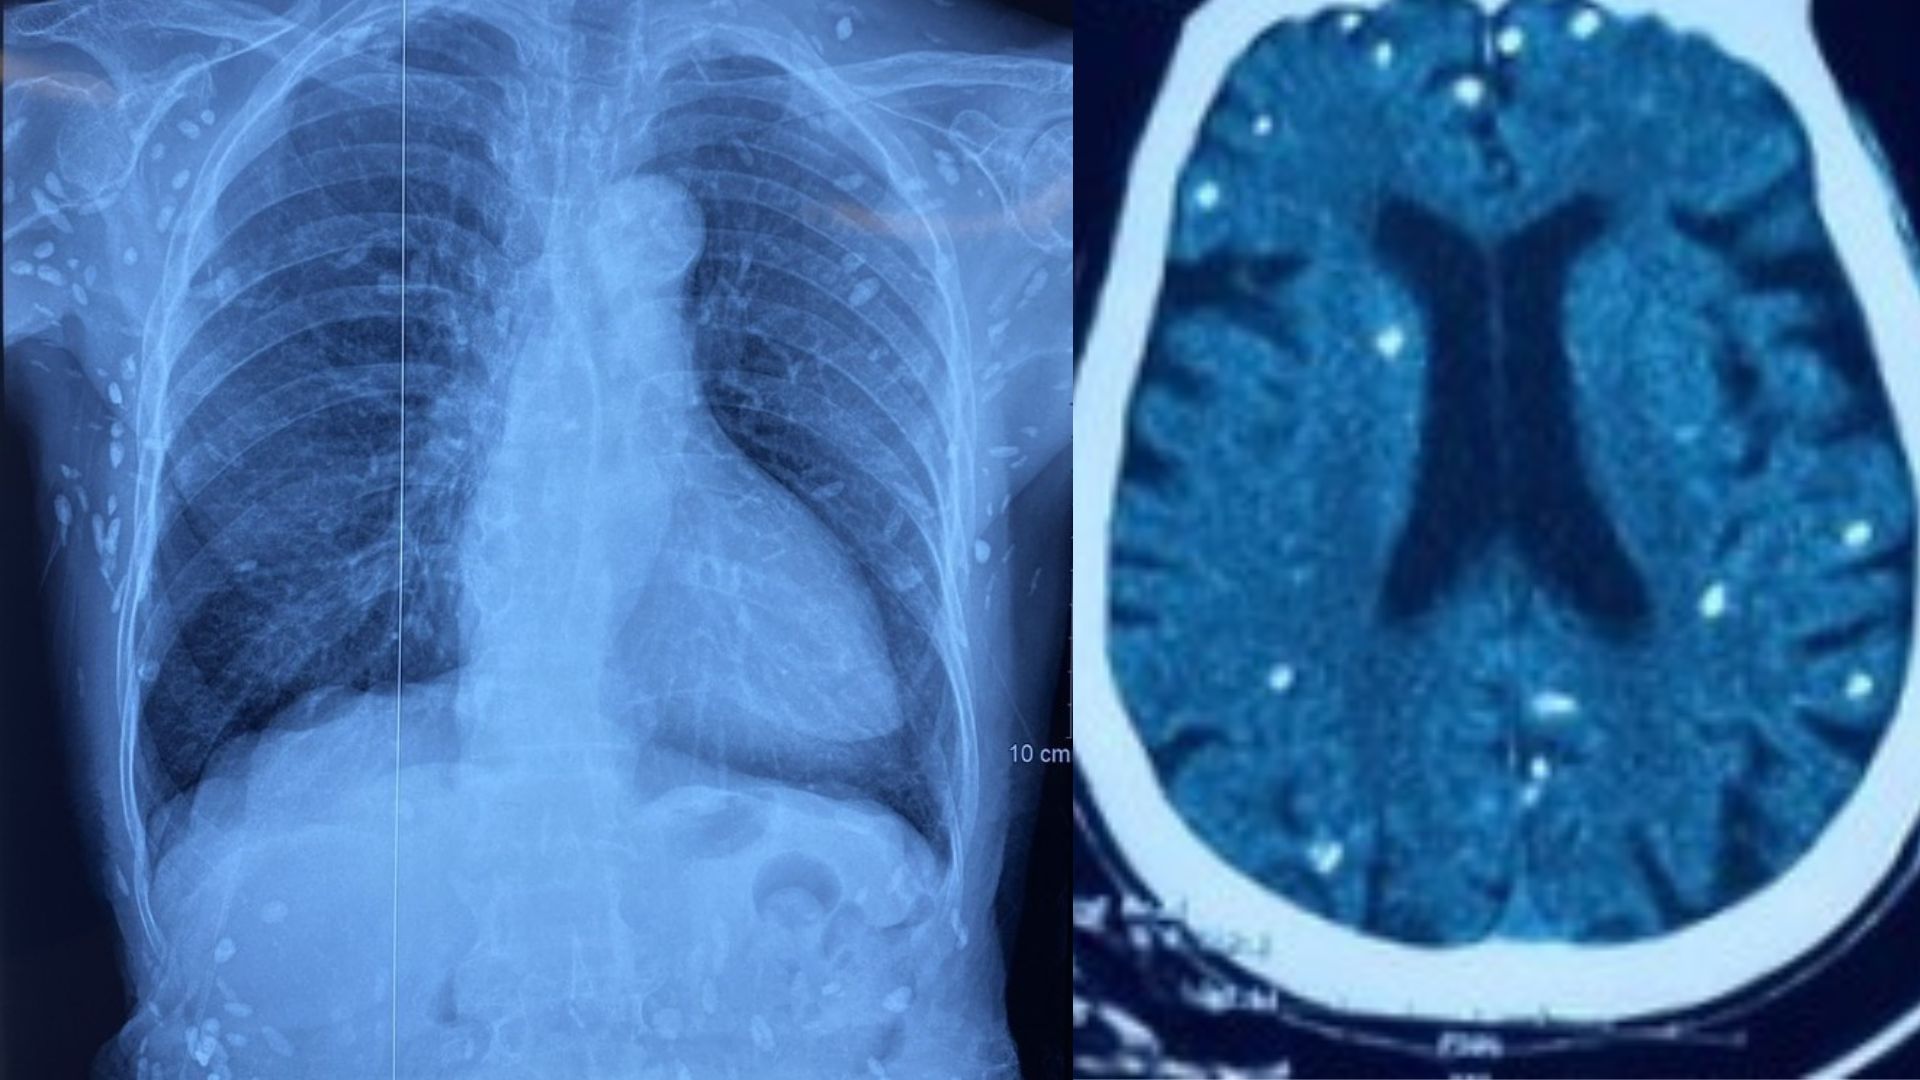

Kết quả chụp cắt lớp vi tính sọ não và X-quang ngực cho thấy nhiều nốt cản quang trong nhu mô não và dưới da vùng ngực – bụng, đặc trưng cho hình ảnh nhiễm ấu trùng sán dây lợn mạn tính. Một số u cục kích thước nhỏ có thể sờ thấy rõ dưới da vùng ngực và cánh tay.

Dù xét nghiệm kháng thể IgM với sán dây lợn âm tính nhưng hình ảnh X-quang vẫn cho thấy các nang sán đã vôi hóa, chứng tỏ người bệnh từng nhiễm ấu trùng từ nhiều năm trước. Các nang này khi thoái hóa thường tồn tại lâu dài trong mô cơ thể. Sau khi được điều trị ổn định theo phác đồ bệnh chính, bệnh nhân đáp ứng tốt và được xuất viện, tiếp tục theo dõi tại tuyến cơ sở.

Hình ảnh X-quang và CT não của bệnh nhân xuất hiện nhiều nốt vôi hóa của ấu trùng sán lợn.

Bác sĩ Thấu cho hay, trường hợp bệnh nhân trên là minh chứng rõ ràng cho hậu quả lâu dài của việc nhiễm sán dây lợn không được phát hiện và điều trị sớm. Khi nang sán thoái hóa và vôi hóa, chúng vẫn tồn tại trong mô, để lại nhiều tổn thương trên phim X-quang hoặc CT não.